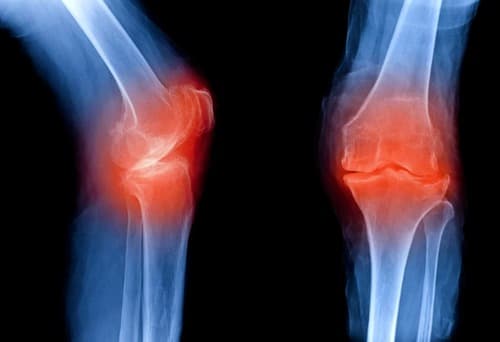

Una de las causas de las enfermedades articulares son los procesos inflamatorios provocados por reacciones autoinmunes, alérgicas en el organismo o por agentes infecciosos. La artritis es un término colectivo para las enfermedades articulares de etiología inflamatoria. Éstos incluyen:

La artritis reumatoide es una enfermedad autoinmune caracterizada por la inflamación de las articulaciones. La causa de la artritis reumatoide son los siguientes factores: genéticos, infecciosos y de partida. Su efecto complejo desencadena un mecanismo autoinmune para el desarrollo de la enfermedad.

La artritis séptica (infecciosa) es una enfermedad en la que se produce la inflamación de las articulaciones debido a la ingestión de un agente infeccioso por vía hematógena (a través de la sangre), linfogénica (a través de la linfa y el sistema linfático) o vía directa (debido a heridas y lesiones). ). Por lo tanto, el foco de infección puede ubicarse no solo en la cavidad articular, sino también de forma remota. La mayoría de las veces, esta enfermedad afecta las articulaciones grandes (monoartritis), pero con la progresión, el proceso puede diseminarse por el cuerpo.

La poliartritis es un proceso inflamatorio que afecta a varias articulaciones de forma simultánea o secuencial. Puede ocurrir como un proceso patológico independiente, o ser consecuencia de enfermedades infecciosas y no infecciosas: sepsis, gota, situaciones de estrés severo y otras.